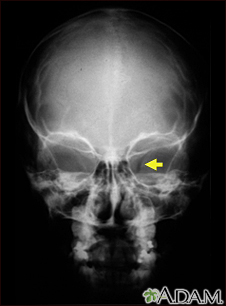

Neurofibromatosis I - enlarged optic foramenBackNeurofibromatosis I - enlarged optic foramenThis x-ray shows the skull of a child with neurofibromatosis (NF-1). This child developed visual difficulties and was discovered to have a glioma (nerve tumor) in the optic nerve. The tumor has enlarged the bony opening (optic foramen), through which the optic nerve passes. This can be seen on the right side of picture. E-mail FormEmail ResultsName:Email address:Recipients Name:Recipients address:Message: